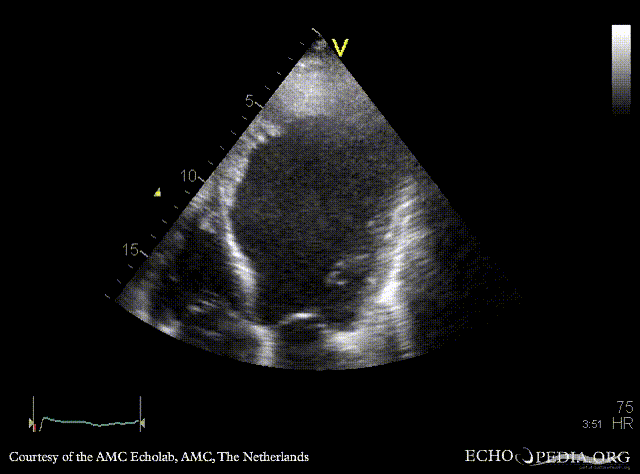

E00221.gif

A2CH: cardiac aneurysm